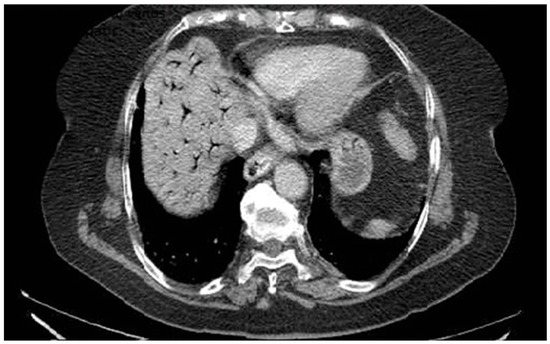

A 76-year-old female patient with no significant past medical history presented with severe upper abdominal pain of more than two days’ duration. On admission, she was hemodynamically unstable, with rapid and acute clinical deterioration of general status and signs ofperitoneal irritation at abdominal examination. Biological markers, including inflammatory parameters and liver function tests, were within normal limits, except for elevated D-dimer levels. Contrast-enhanced computed tomography (CT) revealed extensive gas within the intrahepatic portal venous branches, without evidence of pneumoperitoneum or overt gastrointestinal perforation (Figure 2). The patient was admitted to theintensive care unit for continuous monitoring and intensive resuscitative therapy. Despite supportive management, the outcome was unfavorable, with clinical deterioration precluding surgical intervention. The patient died within 12 h of admission. No necropsy was performed and the underlying cause of portal venous gas remained undetermined. This case highlights several clinically relevant aspects. First, portal venous gas may occur in the absence of overt radiologic signs of perforation or advanced laboratory abnormalities, potentially delaying etiologic clarification. Second, HPVG should be interpreted as a radiologic sign rather than a diagnosis itself; it reflects an underlying pathophysiological process that may range from reversible mucosal injury to catastrophic mesenteric ischemia. Third, from a diagnostic perspective, the absence of visible thrombus emphasizes the distinction between portal vein thrombosis and non-thrombotic portal vein occlusion. Recognizing this difference is essential, as anticoagulation—central to thrombotic PVT management—may not address the primary pathology in HPVG and could even be inappropriate in certain contexts. Therefore, HPVG requires urgent etiologic assessment, multidisciplinary evaluation and individualized therapeutic decision-making.

Figure 2.

Portal Vein Occlusion due to portal venous gas.